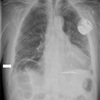

¿Qué proyección es la siguiente?

A

PA